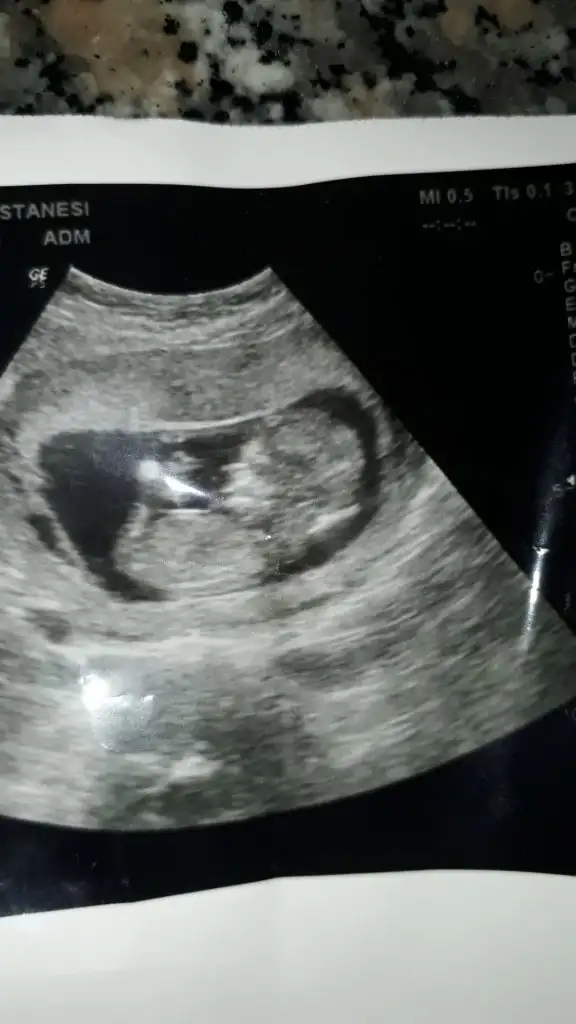

Kizlar benim bebegim erkek. Tum ultrasonlarini attim. Sirasi biraz karisti sanirim. Siz bakip tum teorilere gore karar verin. Nub dan baskasi dogru degil sanki he?

Ramziye gore kiz demislerdir kesin saga yakin bebek diye.

Iste yurt disinda Ramzi teorisi bebegin saga yakinligi diil plasentanin konumuna göre yapiliyor.

Nub teorisinde erkek yorumlamıştım usgnizi